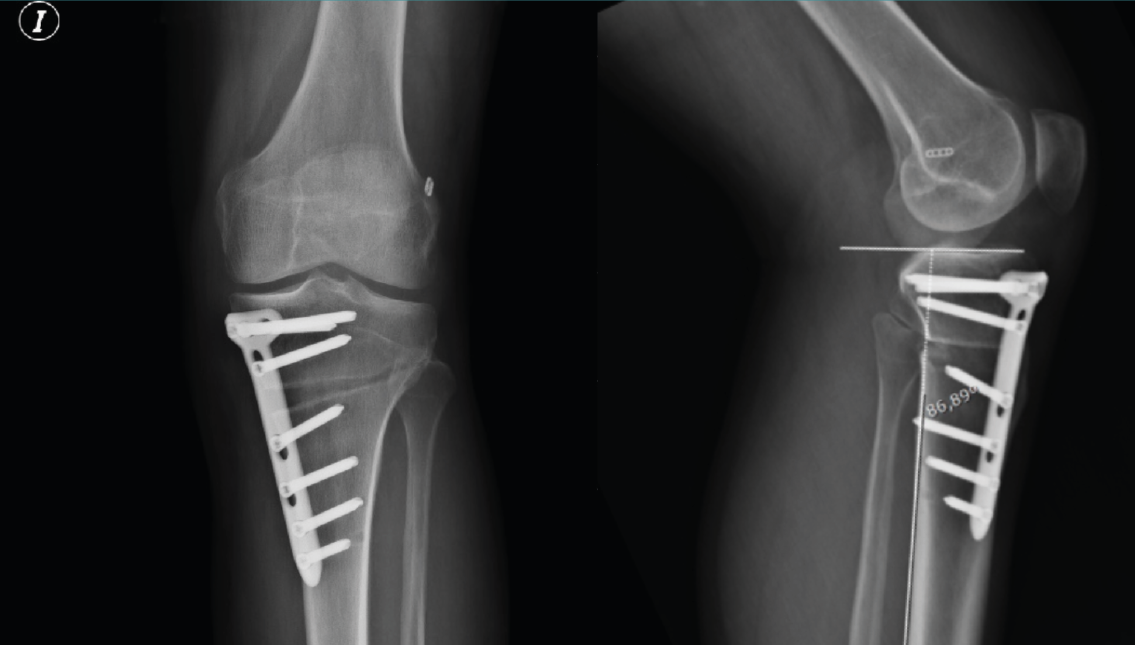

Figura 10. Radiografía de control a los 3 meses en proyecciones anteroposterior y lateral. En la proyección lateral se aprecia que no se modifica la pendiente tibial posterior tras la osteotomía tibial alta de apertura medial.

Uno de los factores de riesgo para la lesión del LCA que ha recibido reciente atención en la literatura es el aumento relativo en la PTP, que es el ángulo formado entre una línea perpendicular al eje mecánico de la tibia y la inclinación superior de la meseta tibial en el plano sagital (Figura 10).

Numerosos estudios radiológicos han establecido una asociación entre una PTP elevada y el aumento del riesgo de lesión del LCA en adultos y población pediátrica(27,32,33). Dejour et al.(27) informaron que por cada aumento de 10° en la PTP se puede esperar un aumento de 6 mm adicionales de traslación tibial anterior, tanto para el LCA intacto como para la rodilla con LCA insuficiente. Durante la carga axial, a través de la articulación tibiofemoral, las fuerzas verticales de corte se convierten en fuerzas de traslación tibial dirigidas anteriormente. El LCA actúa como el restrictor principal para la traslación anterior de la tibia(34), de modo que, a medida que aumenta la PTP, se aplica una mayor fuerza al LCA (o injerto de RLCA) durante la carga funcional(35,36,37).